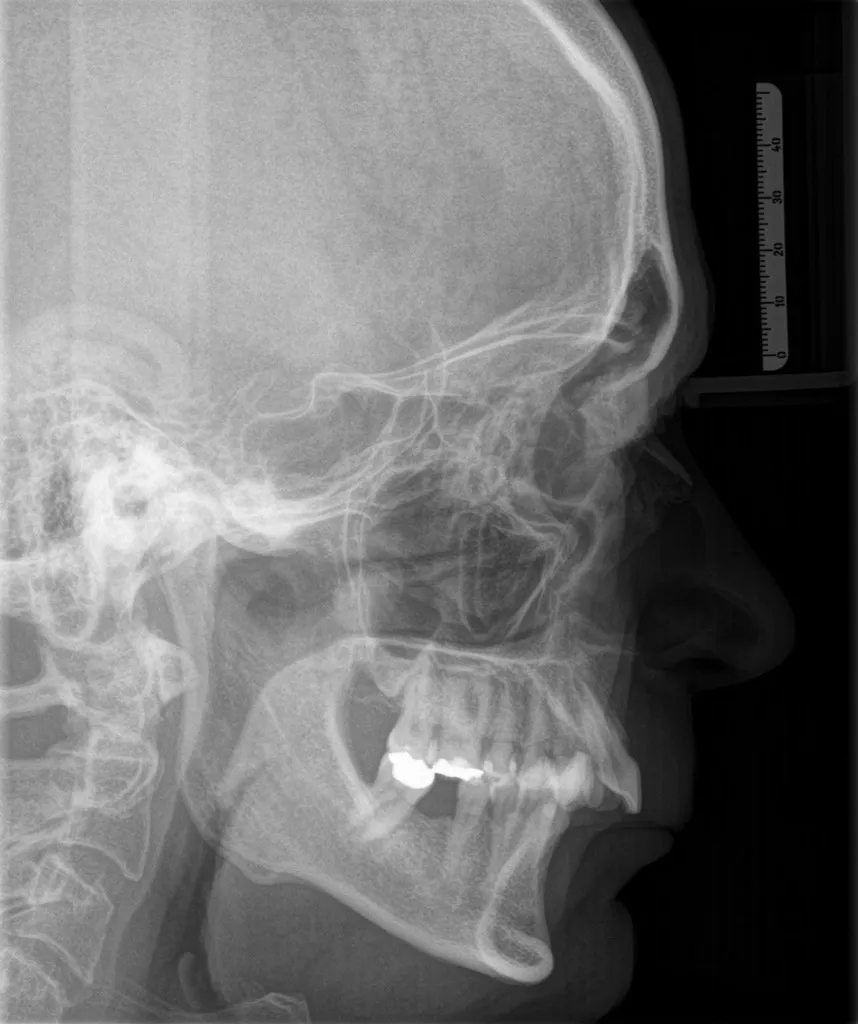

In unserer Praxis ist die kombinierte kieferorthopädisch-kieferchirurgische Behandlung ein zentraler Schwerpunkt. Diese Therapieform eignet sich besonders bei ausgeprägten Kiefer- und Zahnfehlstellungen (Dysgnathien), die nicht nur die Gesichtsästhetik beeinträchtigen, sondern auch funktionelle Einschränkungen wie Probleme beim Kauen, Sprechen oder Atmen verursachen können.

Wenn Ober- und Unterkiefer unterschiedlich stark entwickelt sind, kann nach abgeschlossenem Wachstum eine kombinierte kieferorthopädisch-kieferchirurgische Behandlung notwendig werden. Dabei wird die Position eines oder beider Kiefer chirurgisch korrigiert, um Funktion und Ästhetik nachhaltig zu verbessern.